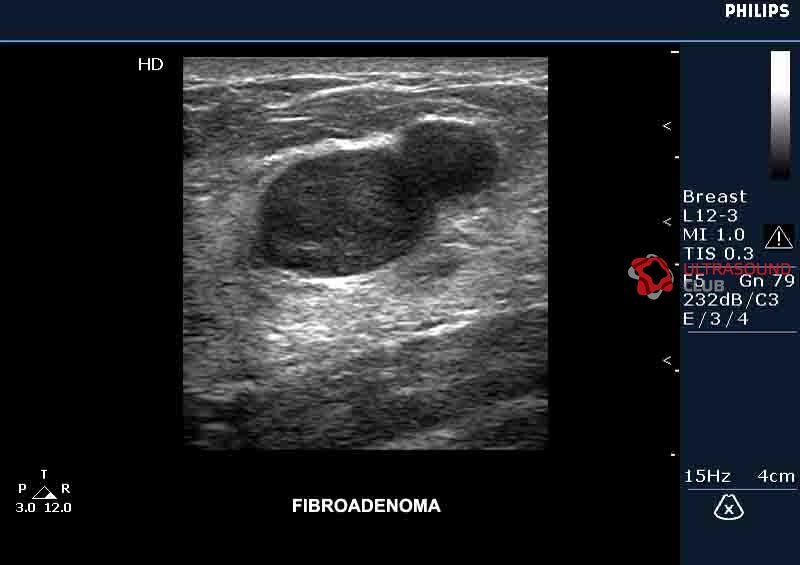

Некоторые фиброаденомы слишком малы, чтобы их можно было почувствовать, но другие имеют диаметр несколько сантиметров. Фиброаденомы часто могут ощущаться как сгусток или гранула в груди. Они обычно круглые и имеют четко очерченные края. Вы можете перемещать их под кожу, и они обычно имеют твердую, эластичную консистенцию, но они не вызывают боль. У женщины может быть одна или несколько фиброаденом. Некоторые фиброаденомы обнаруживаются только с помощью визуализации (например, маммография или УЗИ).

УЗИ молочной железы